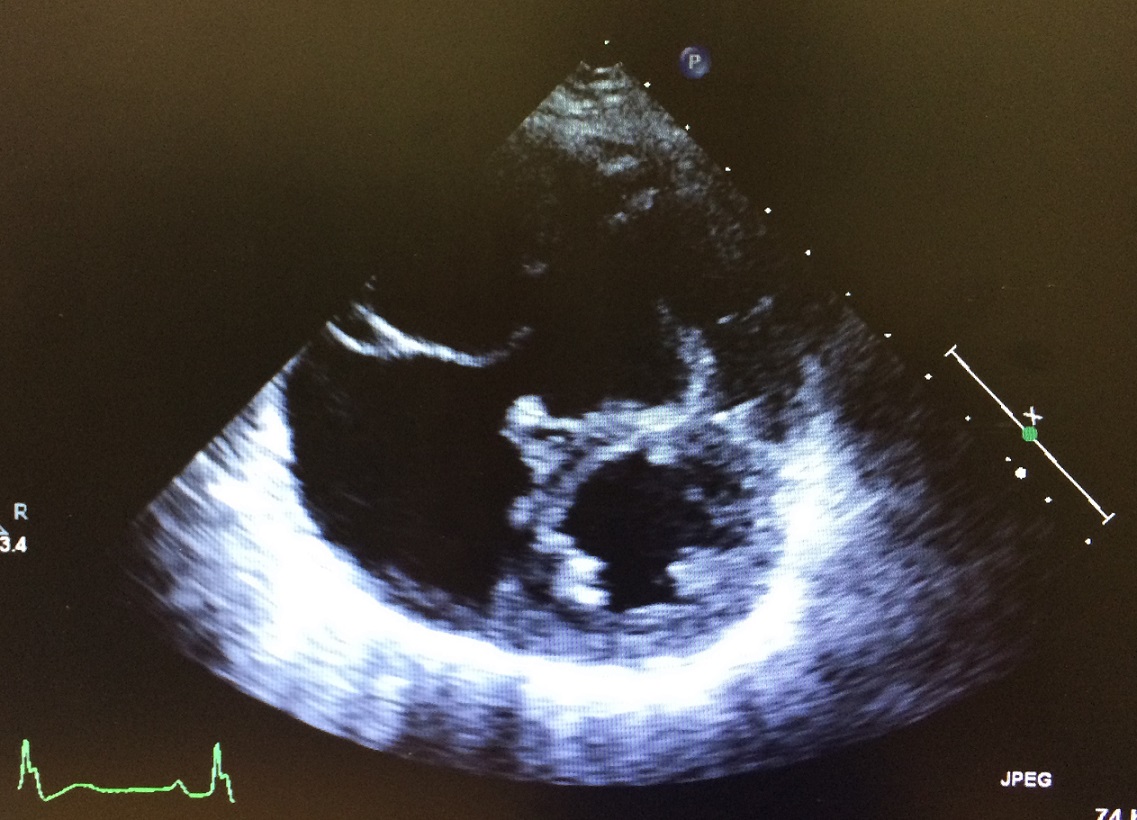

心エコーで見ると、術前は弁が閉じず強い逆流がありましたが、術後は円錐状の弁がきれいに閉じ、逆流がほとんど消失

左写真はMICSで行ったコーン手術の術前(上)と術後(下)の心エコー写真です。三尖弁の逆流が減り、巨大だった右室と右房が著明に改善しています。